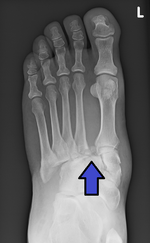

Lisfranc fracture Jacques Lisfranc de St. Martin fracture dislocation of midfoot forced plantar flexion of foot or dropping heavy weight on foot Lisfranc fracture at Who Named It? LisFrancArrow.png